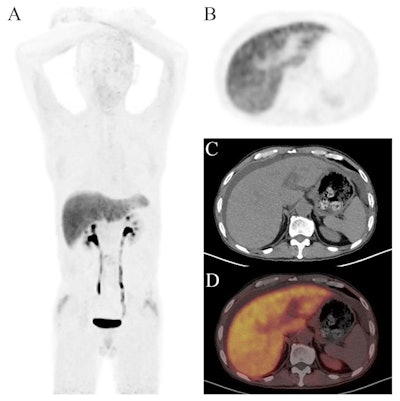

Images of a 55-year-old man with a 10-year history of hepatitis B virus infection. He presented with abdominal distension and yellowing of the skin and sclera for six months. The maximum intensity projection (MIP) image of Ga-68 FAPI-PET/CT showed diffuse tracer uptake in the liver region. Axial images showed significant liver uptake with abdominal effusion (SUVmean = 3.13; TBRliver-to-blood = 2.84; TLfap = 41.3). F4 level of liver fibrosis was confirmed by liver biopsy.Scientific Reports